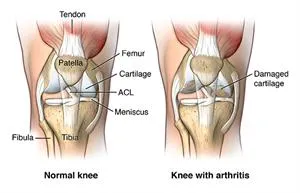

Osteoarthritis is the most common problem that leads to knee replacement surgery. This is a “wear and tear” joint disease that affects mostly middle-aged and older adults. Osteoarthritis leads to the breakdown of joint cartilage, and then bone, in your knees.

Other forms of arthritis, such as rheumatoid arthritis and arthritis caused by a knee injury, can also lead to degeneration of your knee joint. Fractures, torn cartilage, or torn ligaments also can lead to permanent damage to your knee joint over time.